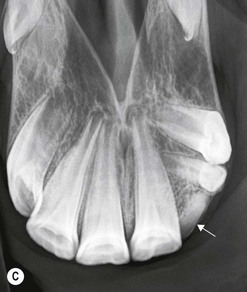

image

(B) Intra-oral radiograph taken intra-operatively during a dental extraction procedure. A small bone-opacity fragment can be seen in the rostral aspect of the alveolus (arrow).

(Radiograph courtesy of W.H. Tremaine.)